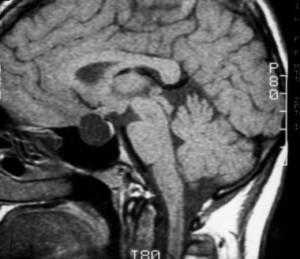

МРТ: киста кармана Ратке. На Т1-взвешенном сагиттальном изображении, полученном до введения контраста, заметно четко очерченное образование в области турецкого седла - с распространением в супраселлярную цистерну. Отмечается гомогенно высокая интенсивность сигнала в образовании по сравнению с паренхимой головного мозга.

Т1-взвешенное сагиттальное изображение, полученное до контрастного усиления: видна хорошо определяемая киста в зоне турецкого седла, изоинтенсивная спинно-мозговой жидкости. Отмечается соответствующая норме высокая интенсивность сигнала задней доли гипофиза сзади.

На Т1-взвешенном корональном изображении она видна рамером чуть менее сантиметра в центральной части турецкого седла. Слегка гиперинтенсивна по сравнению со спинно-мозговой жидкостью.

На этом Т2-взвешенном изображении она изоинтенсивна спинно-мозговой жидкости.

Крупная гиперинтенсивна по сравнению со спинно-мозговой жидкостью на аксиальном протонно-взвешенном изображении. Отмечается расширение турецкого седла с латеральным отклонением чуть заслоненной, но проходимой кавернозной частью внутренней сонной артерии.